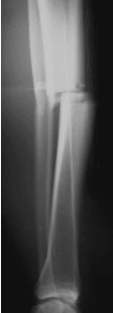

Unterschenkelfraktur mit schwerem Weichteilschaden

nach Quetschung. Zunächst wird die Fraktur mit dem Fixateur

(Monotube) stabilisiert. Erst nach Abschwellen der Weichteile ist

der Verfahrenswechsel zum Verriegelungsnagel möglich. Die primäre

Nagelung ist auch mit einem sogenannten ungebohrten Nagel zu riskant.